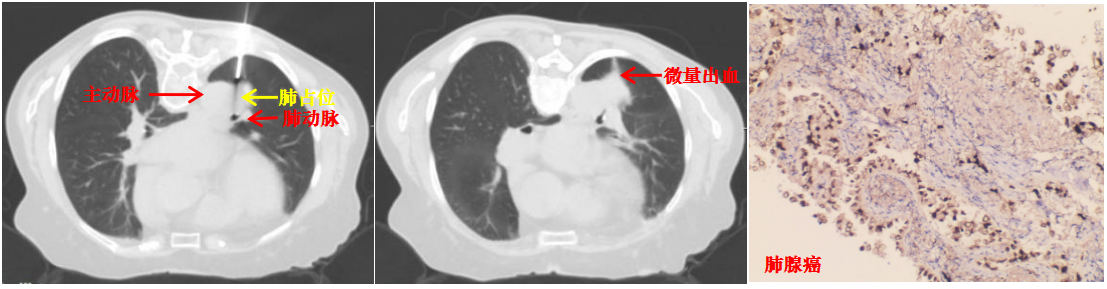

本病例患者肺结节穿刺中(左图)、穿刺后(中图)和病理诊断(右图)

面对诊疗压力与家属的殷切期盼,陆霓虹主任带领呼吸介入团队开展周密术前讨论,反复对患者CT影像进行三维重建和多角度研判,精密测算进针点、角度及深度。同时,针对术中可能出现的咯血、气胸、空气栓塞等并发症,制定了严密的“阶梯式”应急方案。主管医师吴文娟博士及赵思蓉医师用通俗易懂的方式讲解穿刺方案,最终打消了家属的不安与疑虑。

取得患者及家属同意后,陆霓虹主任带领介入团队医生杨嫄、贺晓洁,护士杨红艳、王丽,在CT引导下实施穿刺活检。影像监控下,针尖精准抵达病灶核心,实时测量显示针尖距离主动脉仅4mm,团队迅速完成切割取材,仅出现极少量创面出血,对症处理后患者安返病房,无出血、气胸等并发症。

术后病理确诊为肺腺癌,为患者后续治疗提供了决定性依据。此次技术突破,是科室在高危肺结节诊疗领域的又一跨越。未来,av线上 呼吸与危重症医学科介入团队将持续精进技术、优化诊疗流程,为更多高危肺结节患者提供精准、安全的微创诊疗服务。